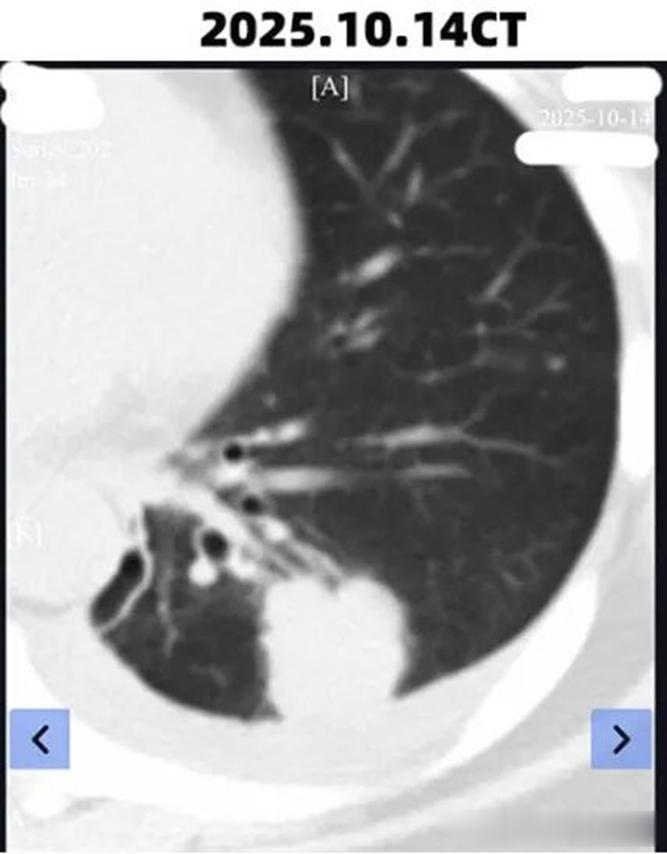

下图是患者在2025年10月14日做的CT。

从图中可以看出,此时的病灶整体较大,30 mm×27 mm×27 mm,且存在叶间胸膜转移。

于是患者采用口服达拉非尼联合曲美替尼的方式进行靶向治疗,约一个月后进行复查。